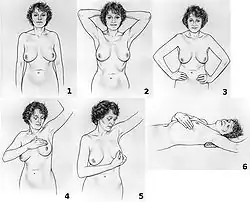

A variety of methods and patterns are used in breast self-exams. Most methods suggest that the woman stand in front of a mirror with the torso exposed to view. She looks in the mirror for visual signs of dimpling, swelling, or redness on or near the breasts. This is usually repeated in several positions, such as while having hands on the hips, and then again with arms held overhead.

The woman then palpates her breasts with the pads of her fingers to feel for lumps (either superficial or deeper in tissue) or soreness. There are several common patterns, which are designed to ensure complete coverage. The vertical strip pattern involves moving the fingers up and down over the breast. The pie-wedge pattern starts at the nipple and moves outward. The circular pattern involves moving the fingers in concentric circles from the nipple outward. Some guidelines suggest mentally dividing the breast into four quadrants and checking each quadrant separately. The palpation process covers the entire breast, including the "axillary tail" of each breast that extends toward the axilla (armpit). This is usually done once while standing in front of the mirror and again while lying down.

Finally, women that are not breastfeeding gently squeeze each nipple to check for any discharge.